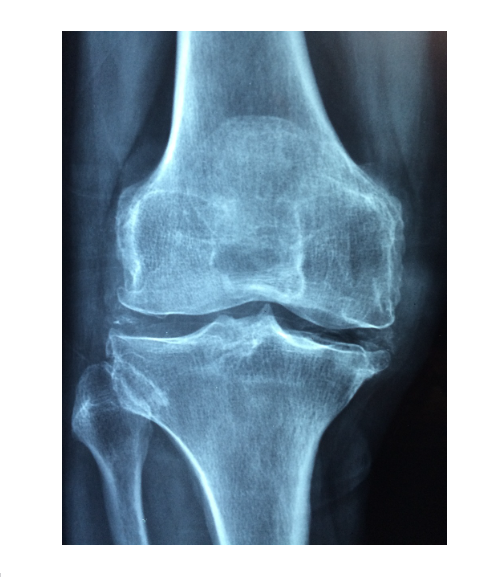

나이가 들면 자연스레 다리도, 허리도 심지어 손가락 마디마디가 쑤시게 되어 여기저기 아프다는 말을 많이 하게 됩니다. 골다공증에 관한 약도 많이 있지만, 먼저 골다공증에 대해 알고 있다면 개선 및 치료에 더 효과적인 도움이 될 수 있다고 생각하여 골다공증에 관한 책 10권을 추천합니다.

골다공증이란 무엇인가? – 골다공증의 정의, 원인, 진행 과정 설명

골밀도 검사와 진단 – 골다공증을 진단하는 방법과 수치 해석